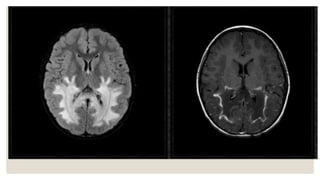

X-ALD – Garland sign

• #60 Adrenoleukodystrophy (ALD) is a x-linked inherited metabolic peroxisomal disorder characterised by lack of oxidation of very long chain fatty acids (VLCFAs) that results in severe inflammatory demyelination of the periventricular deep white matter with posterior-predominant pattern and early involvement of the splenium of the corpus callosum and periatrial white matter changes. Most (85%) patients will demonstrate characteristic MRI findings